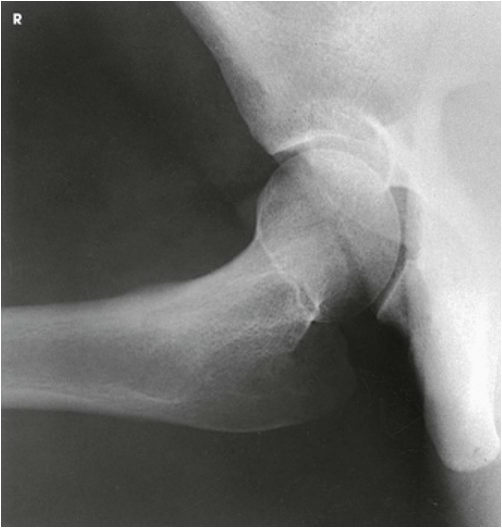

The resulting image shows a lateral projection of the hip, including the acetabulum, the proximal end of the femur, and the relationship of the femoral head to the acetabulum

Lateral Projection; Hip; Lauenstein and Hickey Methods (Lauenstein Method)

Lateral Projection; Hip; Lauenstein and Hickey Methods (Lauenstein Method) (Labeled)